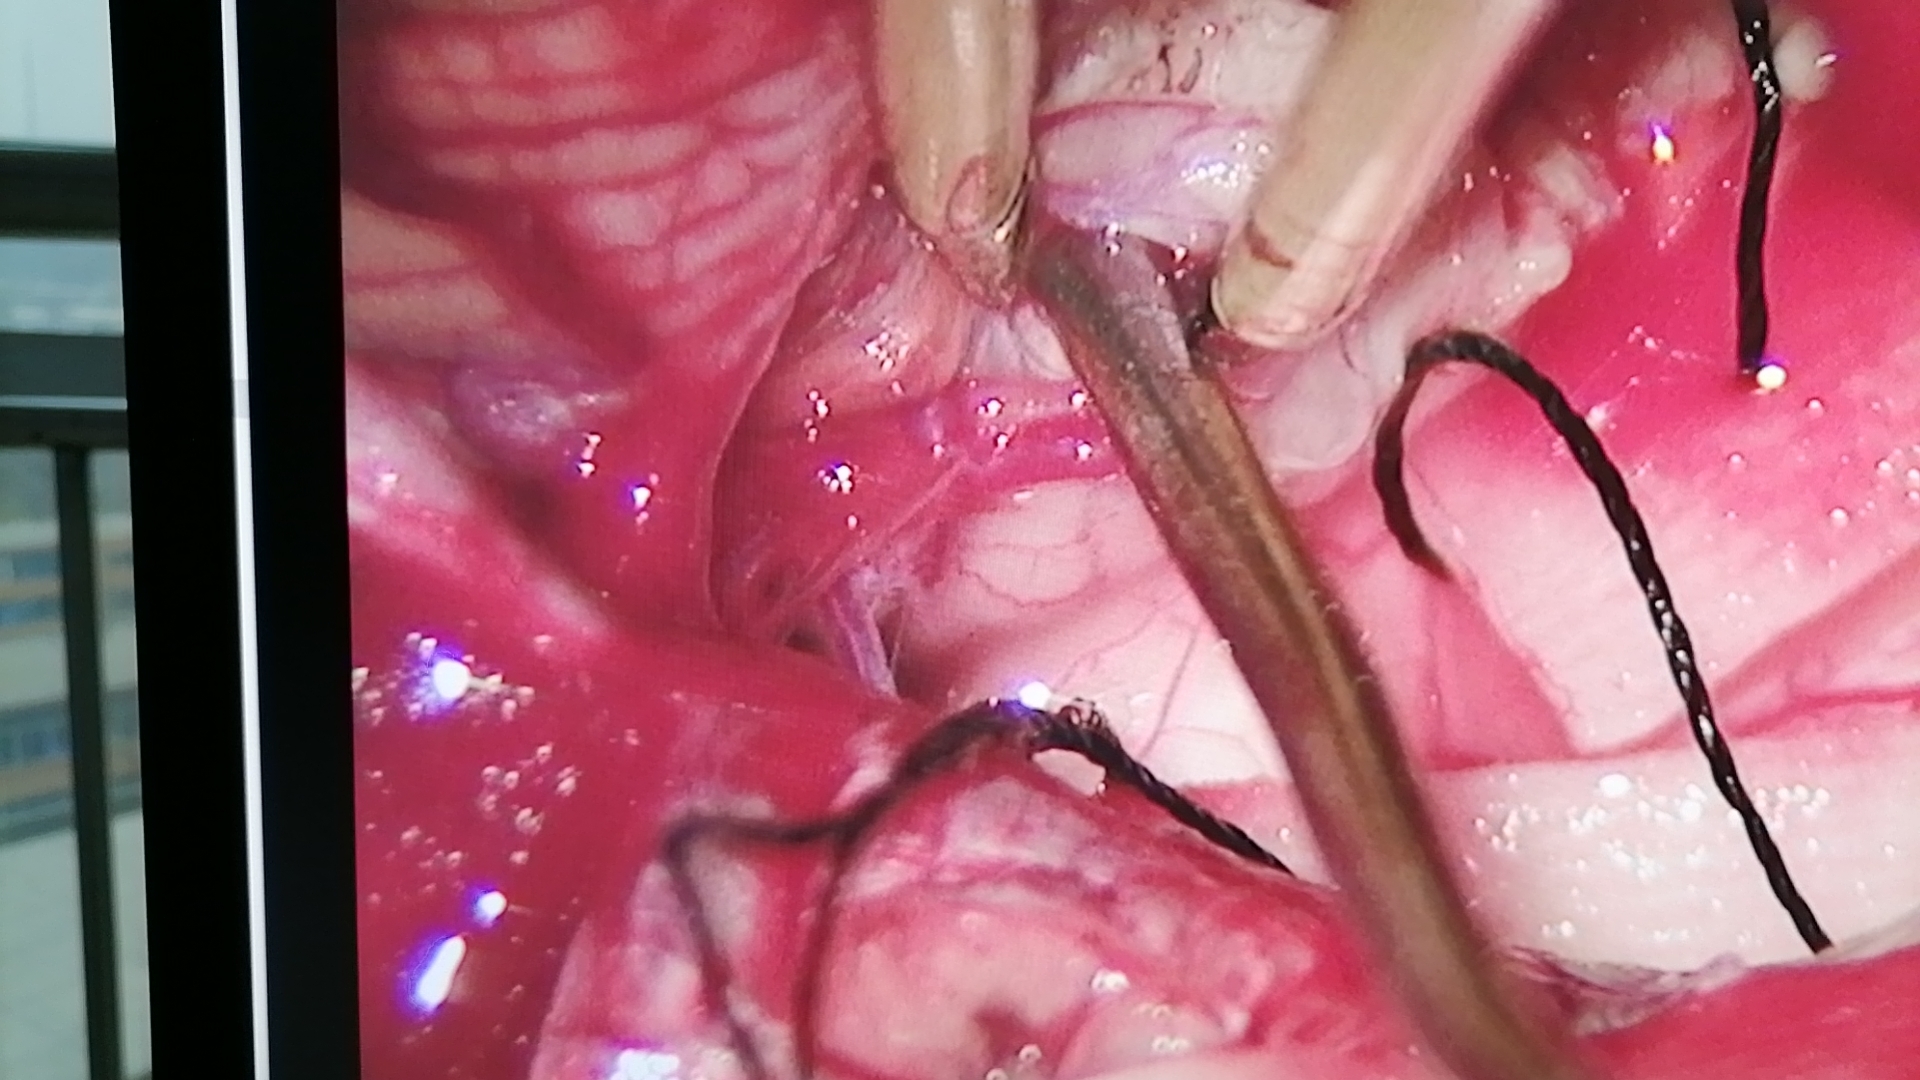

术中情况